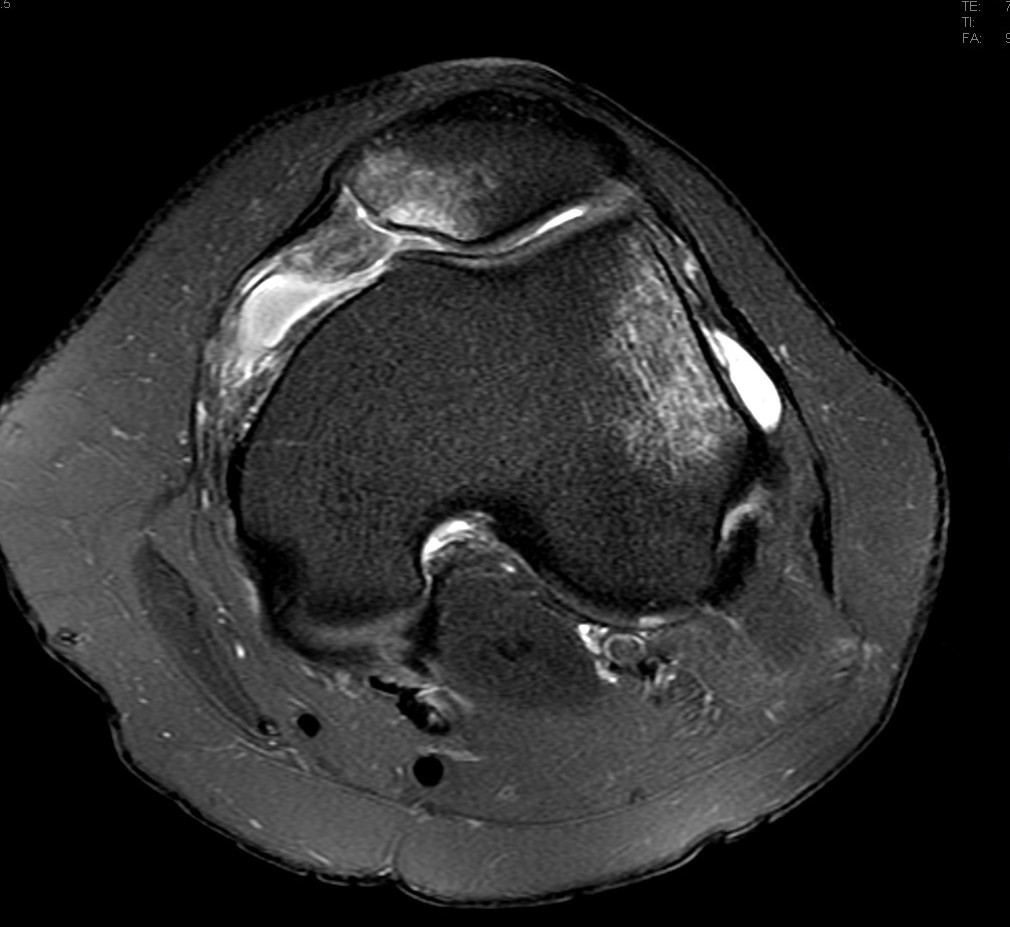

Lateral patellar dislocation

THINGS TO ALWAYS mention in patella injury

• Injury to MPFL

• oestochondral fracture

• patella alta - insall salvati ratio

• should be <1.3.

• Blackburn peel ratio

• normal =0.8

• Patella alta > 1

• Inc TTTG trasnlation distance

• Femoral trocklea displasia

Lateral patellar dislocation refers to lateral displacement followed by dislocation of the patella due to disruptive changes to the medial patellar retinaculum.

MRI

The following features are noted:

medial retinacular abnormalities (ranging from strain to complete disruption) with adjacent periligamentous oedema and haemorrhage

lateral displacement of patella (not necessarily seen in transient dislocation)

medial patellar contusion +/- corresponding lateral femoral condyle contusion

joint effusion

The presence of an abnormal medial patellar retinaculum should suggest the diagnosis of transient lateral patellar dislocation 1.

The images should be scrutinized for the presence of chondral or osteochondral injury, especially if displaced as an intra-articular body, as this may affect surgical management.

The trochlear groove and patella may have abnormal morphology that predisposes to patellar dislocation.